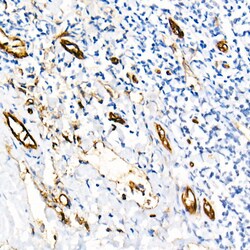

| ELISA, Immunohistochemistry (Paraffin), Western Blot, Immunocytochemistry | |